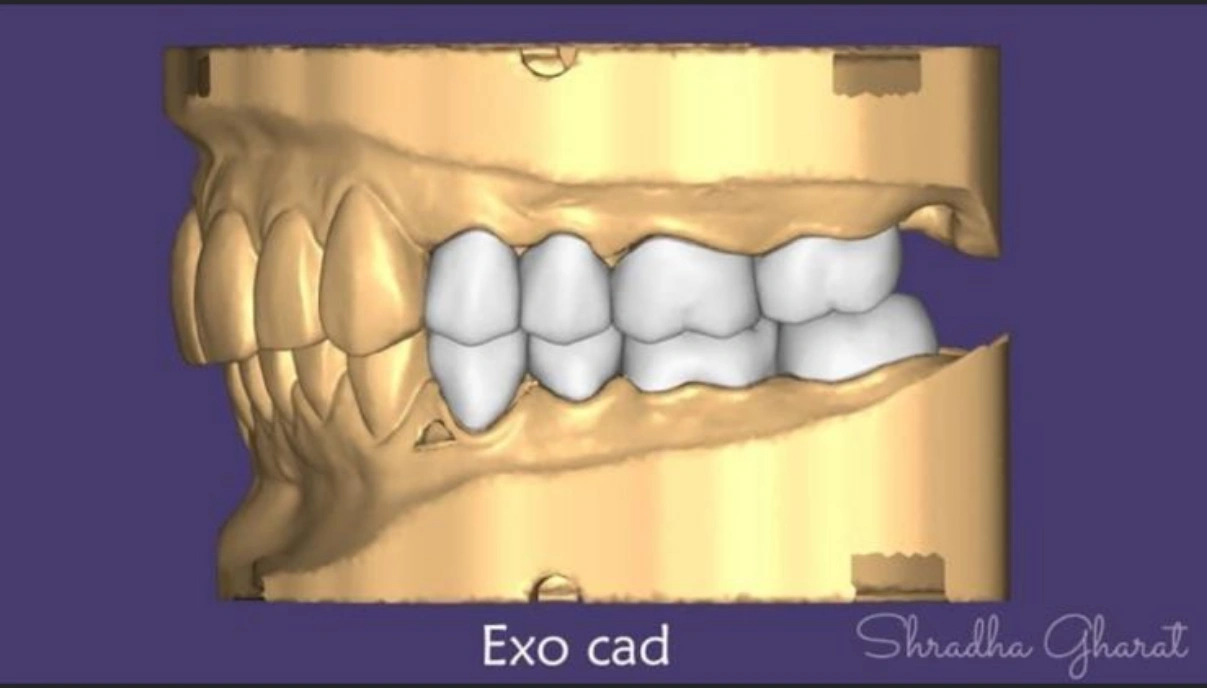

Full mouth rehabilitation includes restoration of lost tooth structure and bite. This technique sensitive procedure involves buildup of lost tooth enamel and dentin. Missing tooth can be replaced with Dental Implants or dental bridges. A Full mouth Reconstruction procedure is mainly indicated for patients with extreme tooth wear.

Full mouth rehabilitation (FMR) is a treatment plan for restoring function and function tolerance of dentition after surgery or dental restoration. It aims to restore dentition to the optimal point of function and esthetics of a healthy mouth. The treatment plan provides patients with a permanent smile that looks natural and bright.

Multiple dental treatments join hands to give you something more than a mere smile makeover. Based on the case history of patient and nature of defects, the following can be advised:-